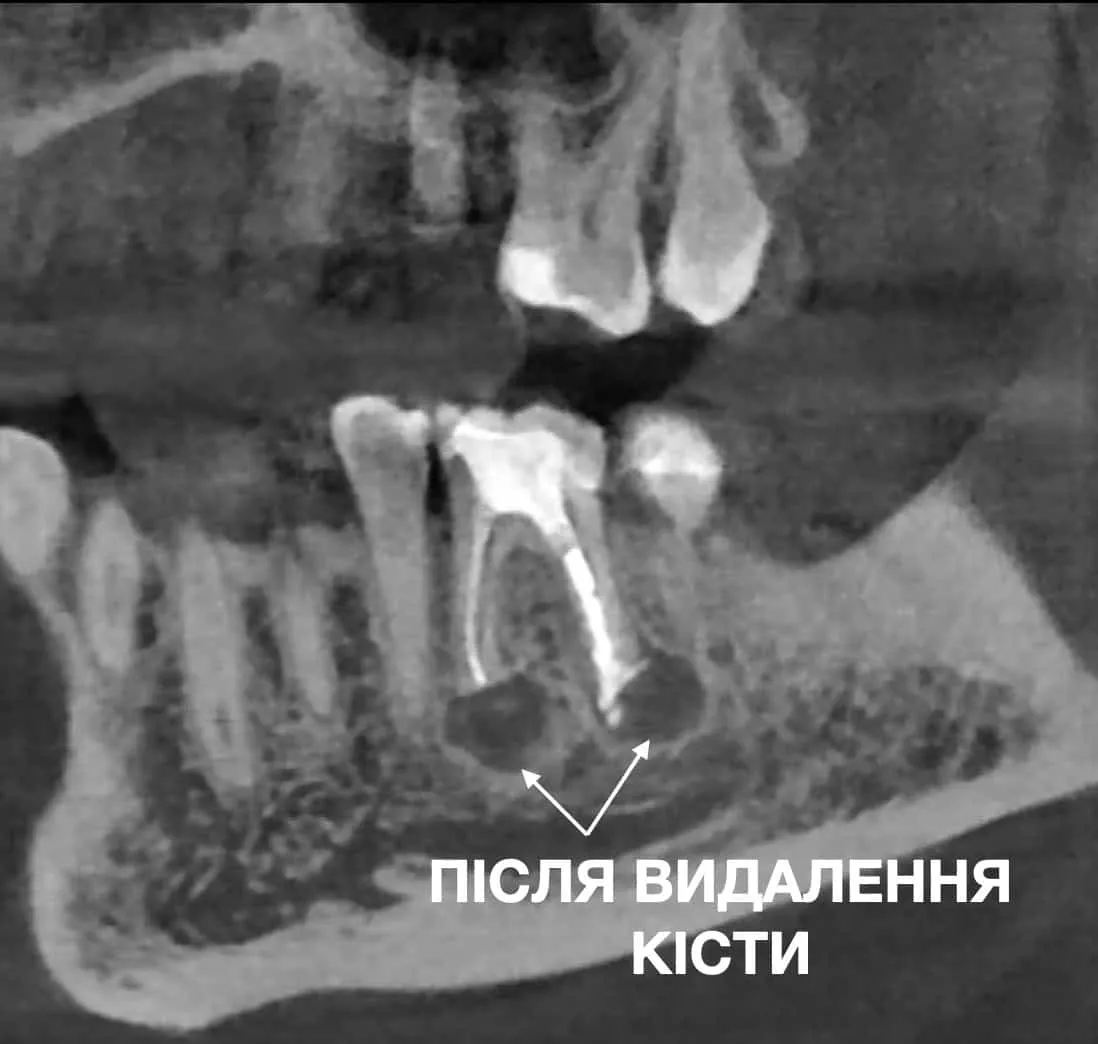

ПРИКЛАД УСПІШНОГО ВИДАЛЕННЯ КІСТИ ЗУБА В СТОМАТОЛОГІЧНОМУ ЦЕНТРІ OLANKO DENTAL STUDIO

Часто апікальна хірургія є єдиним способом уникнути видалення зуба.

Переваги цього методу полягають в тому, що за доволі короткий проміжок часу проходить загоєння рани і досить швидко пацієнт проходить період відновлення. Операція проводиться в одін візит, протягом 1-2 години і ви виходите з тим же цілим, збереженим зубом.